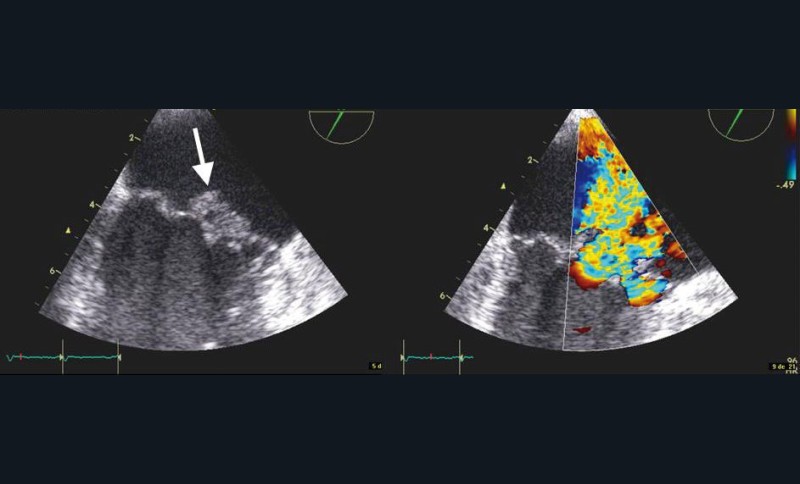

Le dépistage et le traitement des foyers infectieux bucco-dentaires ont toujours été une préoccupation chez les patients présentant une cardiopathie valvulaire en raison du risque d’endocardite infectieuse. Les principales lésions valvulaires sont des mutilations à l’origine de fuites aiguës et des végétations responsables de complications emboliques (fig. 1 et 2).